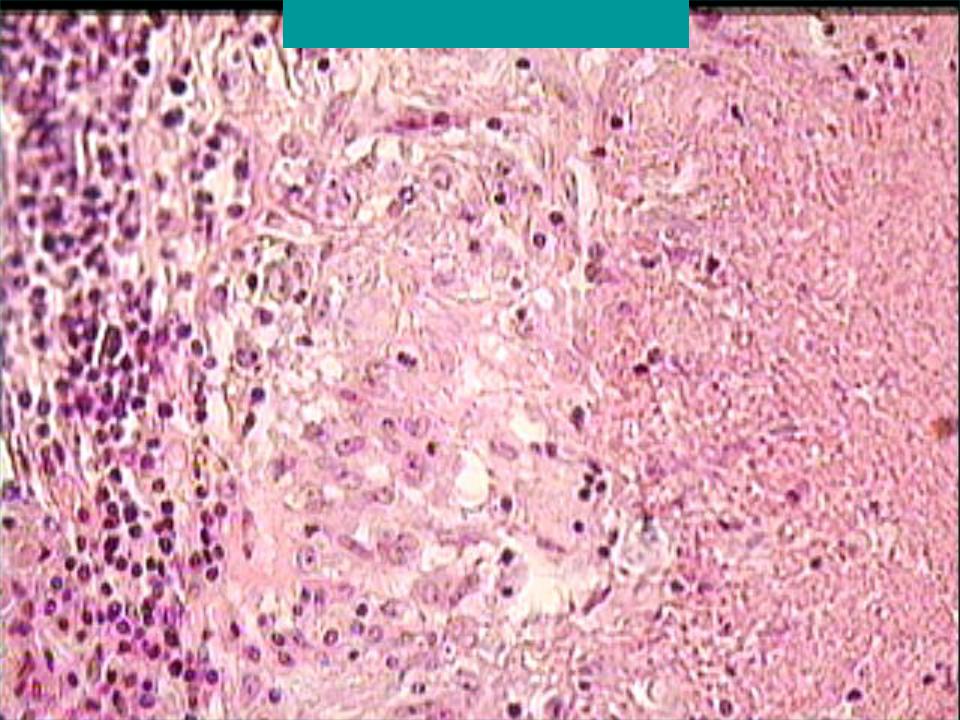

Кольцевидная гранулема – это хроническое доброкачественное заболевание кожи, клинически проявляющееся кольцевидно расположенными папулами (узелками), а патоморфологически – гранулематозным воспалением.

Клинические проявления. Мелкие плотные узелки, слегка возвышающиеся над уровнем кожи группируются в кольца или полукольца разной величины, чаще в виде множественных фигур. Центральная часть колец несколько западает. Элементы имеют цвет нормальной кожи, иногда с бледно-розовым, серовато-красным оттенком.

Преимущественная локализация — тыльная поверхность кистей и стоп, часто около суставов. У детей нередко наблюдается атипичная локализация — на лице, туловище, ягодицах. Очаги поражения могут быть как единичными, так и множественными. В некоторых случаях кожный процесс может носить распространенный и генерализованный характер. Кольцевидная гранулема обычно не имеет чешуек (шелушения) на поверхности и субъективно не беспокоит.

Кольцевидная гранулема может проявляться в виде подкожных очагов (чаще встречается у детей), представляющих собой плотные узлы, безболезненные при пальпации. Типичная локализация — передняя поверхность голеней, пальцы кистей и волосистая часть головы. Кожа над узлами не изменена.

Диагностика. Диагноз кольцевидной гранулемы обычно устанавливается на основании данных клинической картины, но может быть подтвержден при биопсии кожи.